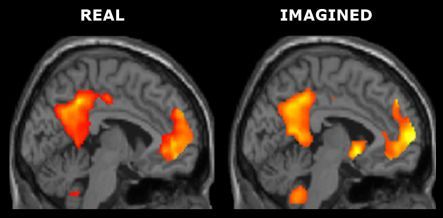

The images in this functional MRI scan of brain activity show the differences between recall of a genuine memory and an invented one.

There are scientists who want to read your mind, and with the aid of an advanced functional MRI scanner, they’re getting closer to actually achieving it. Functional Magnetic Resonance Imaging creates a picture of the brain that allows scientists to see different areas light up as we think, move, remember, and even tell lies. Brett Cowan from the Centre for Advanced MRI and cognitive neuroscientist Donna Rose Addis from the University of Auckland demonstrated the potential, and the limitations, of this technology at a recent event called 'Mind Reading? – The Science of Imaging the Brain'. They show Justin Gregory how they used scans of the brain of a volunteer and attempted to tell the difference between a genuine memory and a made-up lie.